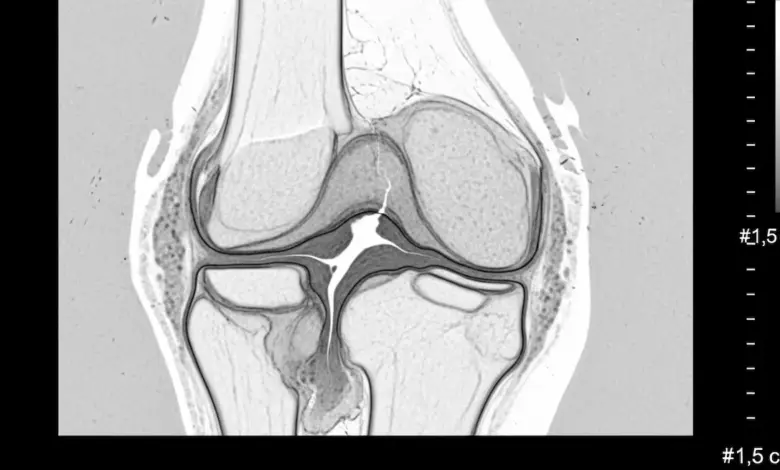

No joelho, esse termo aponta uma perda importante da cartilagem articular, estrutura que reveste as superfícies ósseas, reduz o atrito durante o movimento e protege o osso subcondral.

Em classificações amplamente usadas na ortopedia, as lesões avançadas já representam perda significativa de espessura da cartilagem e, nos quadros mais severos, pode haver exposição do osso subcondral.

A ressonância magnética é o principal exame não invasivo para analisar cartilagem, osso subcondral e extensão do defeito.

Nas lesões mais profundas, o desempenho diagnóstico da ressonância é melhor do que nas alterações muito superficiais.